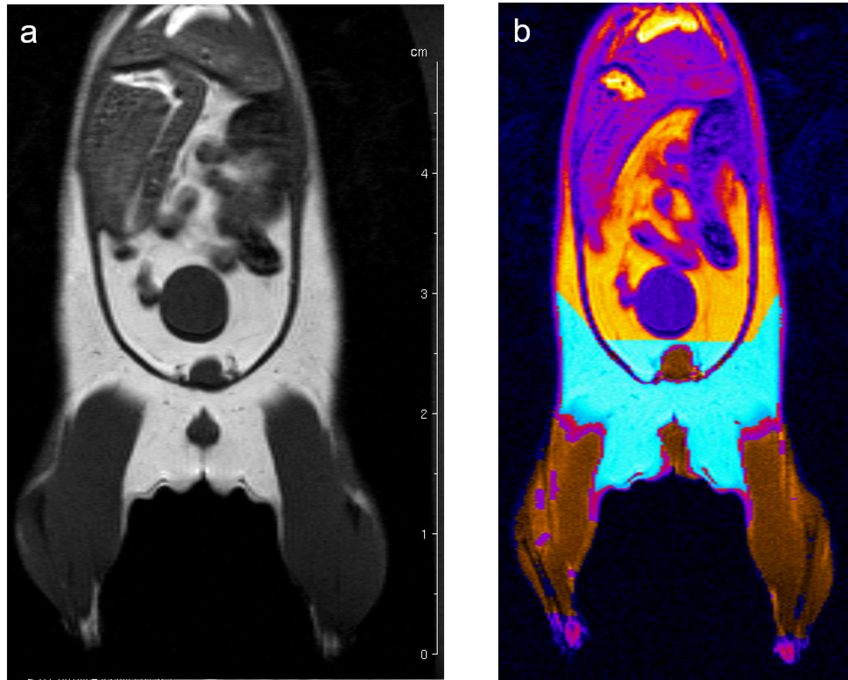

Fat, muscle, tissue-free fluids, and bones generate different signals in response to various radio frequency pulses at distinct magnetic fields, due to their different relaxation properties. We perform MRI studies on mouse using T1-weighted multi-slice-multi-echo (MSME) pulse sequences and analyze the volume of muscle and fat in a well defined and comparable area of the mouse Fig. 6.

Fig. 6: Determination of body fat in mouse. (a) A MSME sequence with a repetition time of 452 ms, echo time of 8.6 ms, field of view 7.0x7.0 cm2 covering the entire body and lower legs, a matrix of 512x256 and slice thickness of 1.0 mm was used to acquire 20 coronal slices with1.0 mm slice thickness and 1.0 mm interslice distance. (b) After evaluation the region in cyan represents the quantified fat and the region in brown the quantified muscle volume.